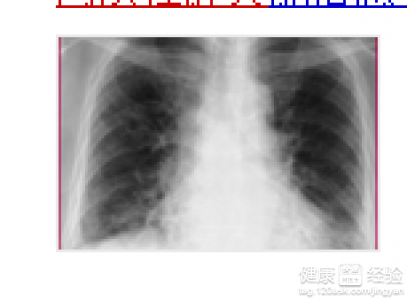

陕西可靠的肺间质性肺炎治疗推荐_全套肺间质性肺炎

什么是间质性肺炎,便利的肺间质性肺炎,间质性肺炎怎么治疗,全套肺间质性肺炎,西安间质性肺炎 想了解其它相关信息,欢迎登录西安华中医院呼吸病诊疗中心网站或电询我们相关人员。

华中医院呼吸病诊疗中心提供的肺间质性肺炎治疗主要是针对患肺间质性肺炎的人群的,治疗周期大概为1-30天。我机构始终秉持着中医治疗,打通经络,清肺排毒,化痰定喘,肺腑穴位贴药,配合煎药泡脚的特色服务,所提供的肺间质性肺炎治疗在西安市拥有很高的认知度。